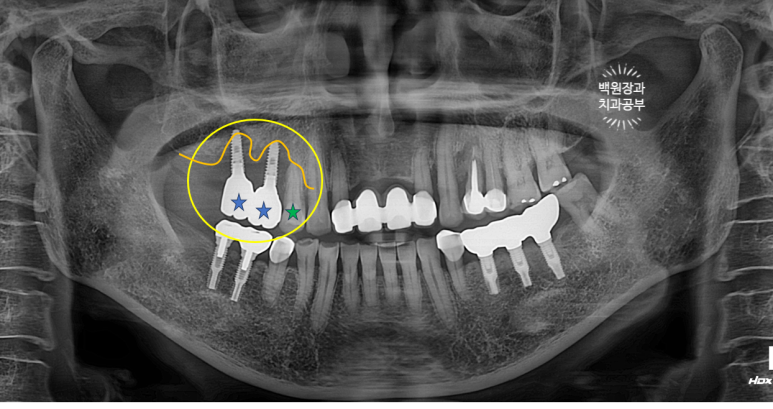

오른쪽 위 임플란트 2개를 약 10년 전에 수술하신 분입니다.

노란색으로 동그라미 쳐져 있는 부위의 임플란트 주변 잇몸에서 고름이 나온다고 하셨어요.

이미 잇몸뼈는 주황색 선처럼 매우 많이 사라져 버린 상태..... 이미 임플란트 주변 뼈는 모두 사라져 빠지기 직전.

보시면 녹색 별로 표시한 자기치아도 주변 뼈가 이미 많이 없어진 것을 보실 수 있습니다.

임플란트 주위염이 심해지면 주변 자연치아도 못쓰게 됩니다. 정기검진을 꼭 다니셔야하는 이유입니다.